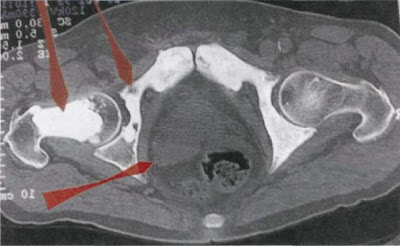

He incluido en el texto esta imagen y las siguientes porque ilustran muy bien la locura de los diagnósticos de la medicina tradicional.

Este paciente de 64 años, va a un urólogo desde hace años para hacer controles de la próstata (conflicto: divorcio, nuevo matrimonio...). A causa de estas fotografías un día el doctor se le presentó con una cara larga y le explicó que le quedaban pocas semanas de vida, que todo el vientre estaba lleno de metástasis (entiéndase la mancha blanca). El informe del radiólogo había hablado de “metástasis osteoblástica”. Con eso ya se había pronunciado la condena a muerte. Cuando el paciente vino a mí con sus lastras durante un seminario en Mallorca, le pude explicar cosas que lo alegraron mucho. Seguidamente nos reímos mucho juntos.

El lóbulo posterior, agrandado, de la próstata (flecha de abajo a la izquierda) está atravesando una tuberculosis líquida caseosa (sudor nocturno) y produce temporalmente un desplazamiento del recto de la posición central hacia la derecha.

Los puntos óseos blancos (por ej. la flecha de arriba) son ex-osteolisis recalcificadas y muestran que el paciente, que ahora está de nuevo felizmente casado, ha resuelto positivamente su conflicto de autodesvalorización (“en el vientre ya no valgo nada”). Eso no excluye que (flecha de arriba a la derecha) no pueda sufrir una nueva y pequeña osteolisis coincidiendo con una nueva recaída en las zonas recalcificadas.

De candidato a la muerte, en el giro de unos pocos minutos, volvió a ser un hombre alegre que seguía preguntándose desconcertado: “Doctor, ¿de verdad cree que todo está ahí?”.

Para estos pacientes, literalmente asustados por la muerte misma, es mucho más difícil tener la certeza de volver a estar sanos (en este caso: recién cuando termine la intensa y floreciente TBC ), solo por el hecho de creer, a pesar que nunca han estado realmente enfermos, en una muerte inevitable, que vendrá al cabo de unas pocas semanas.